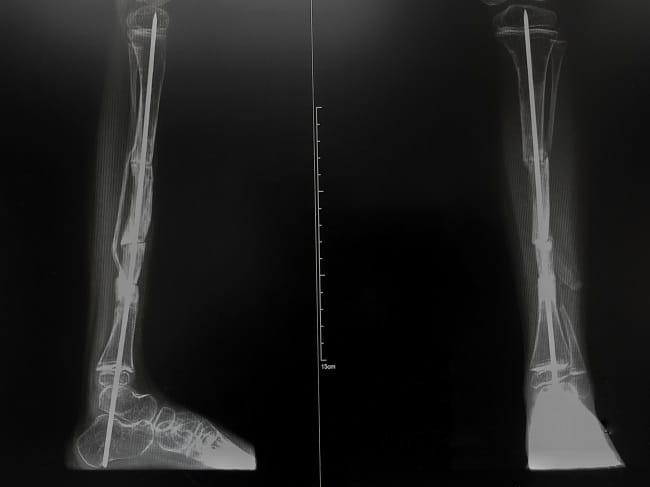

- Foto Rontgen, untuk memeriksa patah tulang atau kelainan pada tulang

Operasi umumnya dilakukan pada pasien yang mengalami patah tulang berulang kali dan memiliki kelainan pada bentuk tulang. Misalnya, dokter akan melakukan operasi tulang belakang pada pasien osteogenesis imperfecta yang mengalami skoliosis. Dokter juga dapat melakukan operasi rahang untuk memperbaiki posisi rahang.